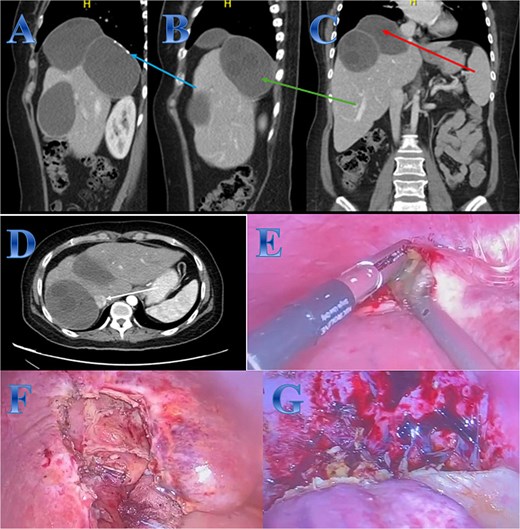

Case 3

A 54-year-old woman presented with upper abdominal pain with a history of PAIR procedure before 5 years. The abdominal CT scan with contrast highlights left hepatic lobe calcified exophytic CE (Fig. 3).

Case 3. (A) Coronal CT cut of the abdomen at venous phase showing a well-defined cystic lesion (hydatid cyst) seen at the left hepatic lobe, showing calcifications, the lesion seen partially exophytic from the liver and abutting the lesser curvature of the stomach. (B & C) The hydatid cysts that were resected from the liver (C) and from the greater Omentum (B). (D) After resection the liver hydatid cyst was opened to examine the content of the cyst which is showing jelly like structure.

For a left lateral hepatic resection, a subcostal incision allowed exploration of the calcified cystic mass, which affected segments 2 and 3 of the liver and was significantly adhered to the diaphragm and stomach. A left lateral segment (segments 2 and 3) mobilization procedure required dividing the falciform, left triangular, and left coronary ligaments. A harmonic scalpel, in combination with bipolar coagulation, completed the resection of the recurrent hydatid cyst without damaging its internal contents (Fig. 3).